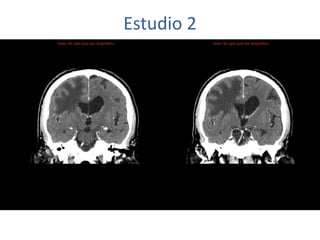

Estudio 2

• Estudio sin y con contraste, con reconstrucciones sagitales y coronales

del estudio con contraste.

Se observa una lesión ocupante de espacio en lóbulo frontal derecho que

presenta un tamaño de 18 x 32 x 22 mm (cc x ap x tr), bilobulada, no del

todo bien delimitada, con realce en anillo irregular, con hipocaptación

central, probablemente por necrosis, y asociada a un extenso edema

vasogénico con efecto masa tanto sobre los surcos de la convexidad

como sobre la cisterna insular, el sistema ventricular y la línea media,

esta última con un desplazamiento de 5 mm a la altura del septo

interventricular.

No se aprecian otras lesiones focales intra o extraaxiales de significación

patológica.

Habría que considerar como primera posibilidad que se tratase de una

lesión metastásica, por bien un tumor primario, aunque no se puede

descartar otras opciones, sin imprescindible correlación con la clínica y

con sus antecedentes.